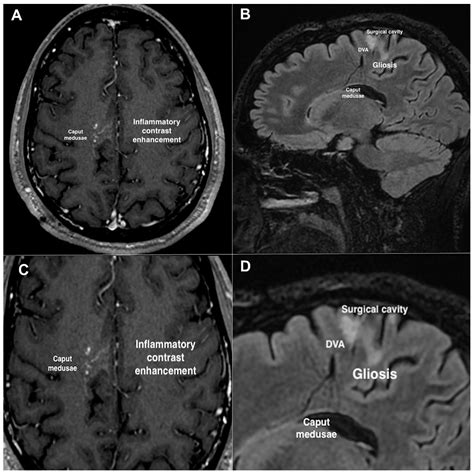

A Developmental Venous Anomaly is essentially a collection of small, radially arranged medullary veins that converge into a single, enlarged central draining vein. This pattern is often referred to in radiological literature as a “caput medusae,” resembling the head of Medusa from Greek mythology. These structures exist to provide venous drainage for healthy brain tissue in regions where the normal deep or superficial venous systems may not have formed correctly during fetal development.

The standard for evaluating a Developmental Venous Anomaly is Magnetic Resonance Imaging (MRI). On T1-weighted images, the DVA may appear as a subtle enhancement, while on T2-weighted or susceptibility-weighted imaging (SWI), the enlarged draining vein becomes very prominent due to the deoxygenated blood flow.

• Contrast administration: Gadolinium is often used to visualize the “caput medusae” pattern clearly.